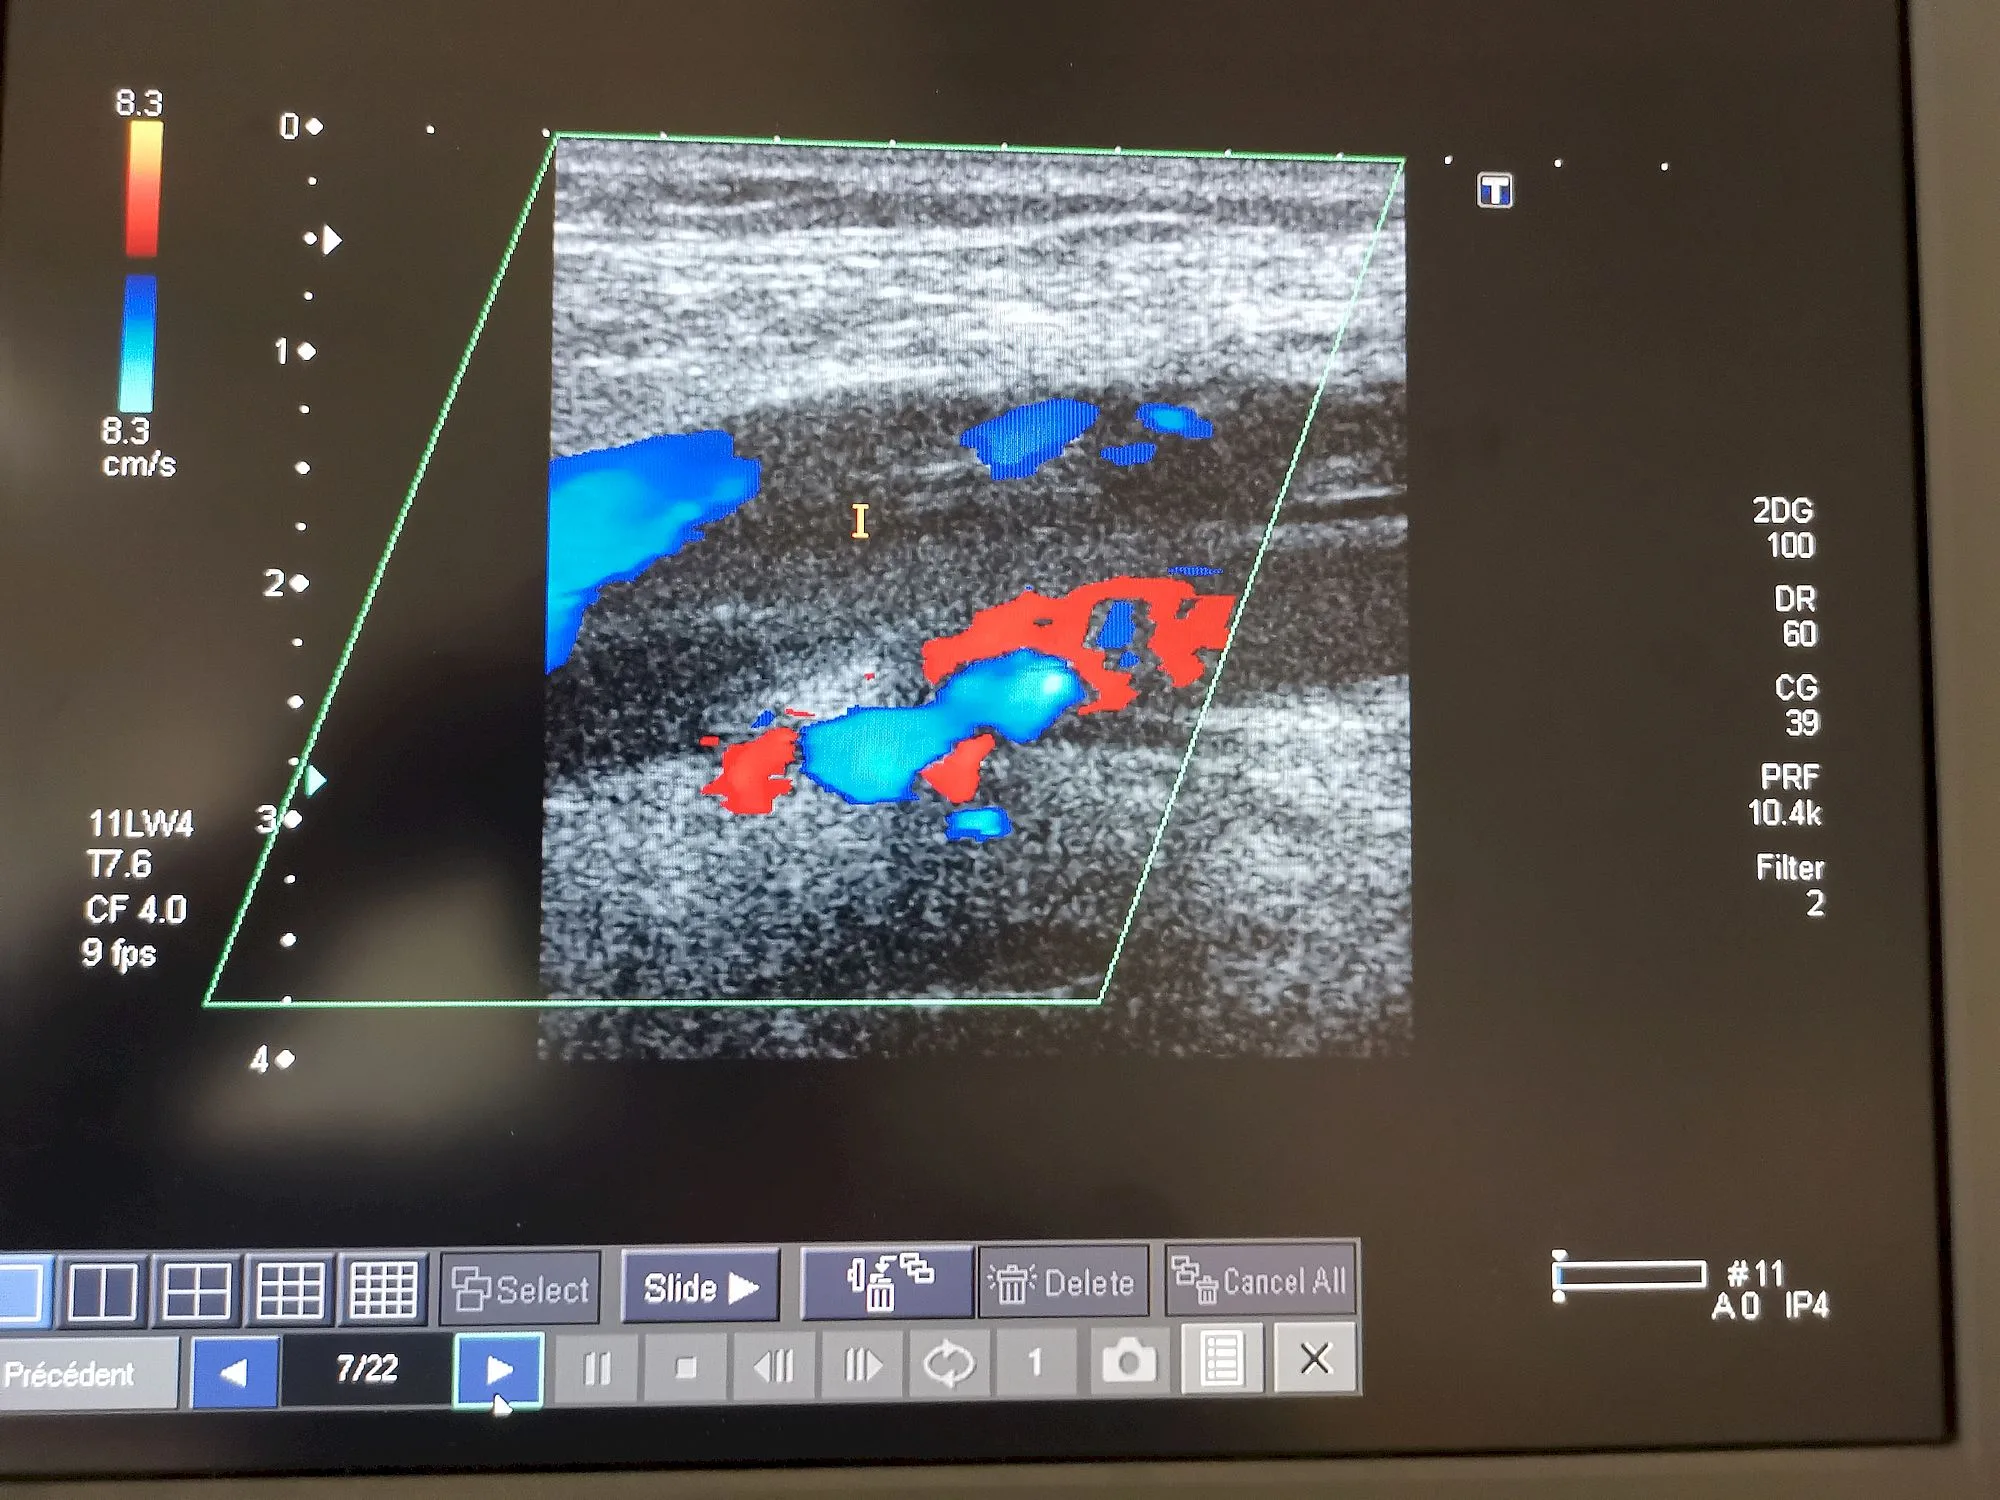

il faut traiter les patients le début , et la confrontation avec les problèmes de coagulation, des phlébites ,et même des embolies pulmonaires,

La découverte de l’équipe du Professeur Eric Delabrousse au CHU de Besançon va vraisemblablement permettre de sauver davantage de vies parmi les patients Covid-19 gravement touchés au plan respiratoire. Grâce à un angioscanner pulmonaire qui révèle les embolies pulmonaires non détectées jusqu’alors.